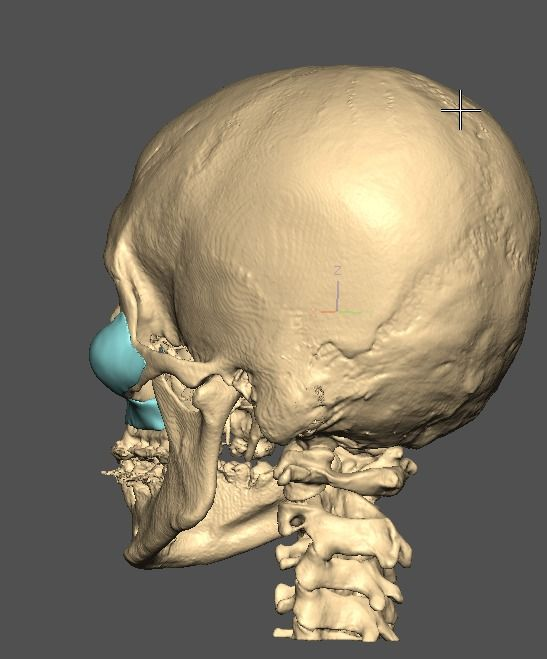

I know a guy who designed this for himself in collaboration with an asian implant company.

Not the final product yet, he is making adjustments as we speak.

Found a surgeon willing to insert it.

Giant and Eppley were the inspiration